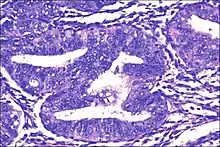

| Micrograph showing simple endometrial hyperplasia, where the gland-to-stroma ratio is preserved but the glands have an irregular shape and/or are dilated. Endometrial biopsy. H&E stain. | |

- Endometrial hyperplasia (simple or complex) - Irregularity and cystic expansion of glands (simple) or crowding and budding of glands (complex) without worrisome changes in the appearance of individual gland cells. In one study, 1.6% of patients diagnosed with these abnormalities eventually developed endometrial cancer.[5]